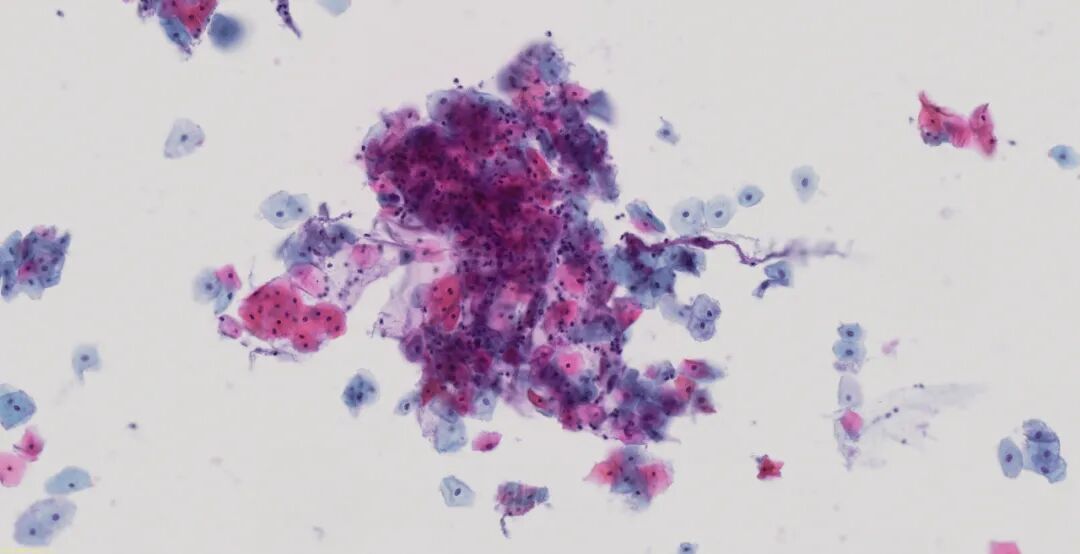

您多年來一直信賴的光學(xué)品質(zhì)如今已體現(xiàn)在專用玻片掃描系統(tǒng)中。基于病理學(xué)成像領(lǐng)域深厚的專業(yè)知識(shí)而打造,為組織學(xué)和細(xì)胞學(xué)樣品提供顯微鏡質(zhì)量的圖像。可驗(yàn)證的數(shù)字成像流程,系統(tǒng)化的色彩再現(xiàn)評(píng)估方法讓真實(shí)顏色準(zhǔn)確再現(xiàn)。

清晰捕捉細(xì)胞學(xué)樣品的圖像

清晰捕捉各種組織和染色的細(xì)節(jié)